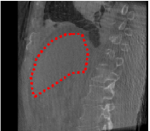

An example of CT/CBCT and MR/CBCT registration results are shown in figures 3 and 4, respectively. For both cases, the CBCT image (first column) was acquired intra-operatively after needle insertions and was employed as a reference for image registration. The pre-operative image is displayed before registration (second column), after PM-EA (third column) and after PM-EA+Evo (fourth column). The occurrence of patch shifts is reported for each spatial direction in panels (m–o): for each histogram, the shift with maximal occurrence is shown by the red dashed line. For panels (a–l), a ROI — manually defined on the CBCT image/encompassing the liver — is shown using red dash lines. Our visualization shows an improved correspondence of the contour of the liver with the manually defined liver boundary when the PM-EA solution is employed (see 3(c,g,k) and 4(c,g,k)). Moreover, an even better correspondence of the contour is observable using the PM-EA+Evo solution (see 3(d,h,l) and 4(d,h,l)).

Trans.

[X-Y]

CBCT

(a)

MRI / No registration

(b)

MRI / PM-EA

(c)

MRI / PM-EA+Evo

(d)

Sag.

[X-Z]

(e)

(f)

(g)

(h)

Cor.

[Y-Z]

(i)

(j)

(k)

(l)

(m)

(n)

(o)